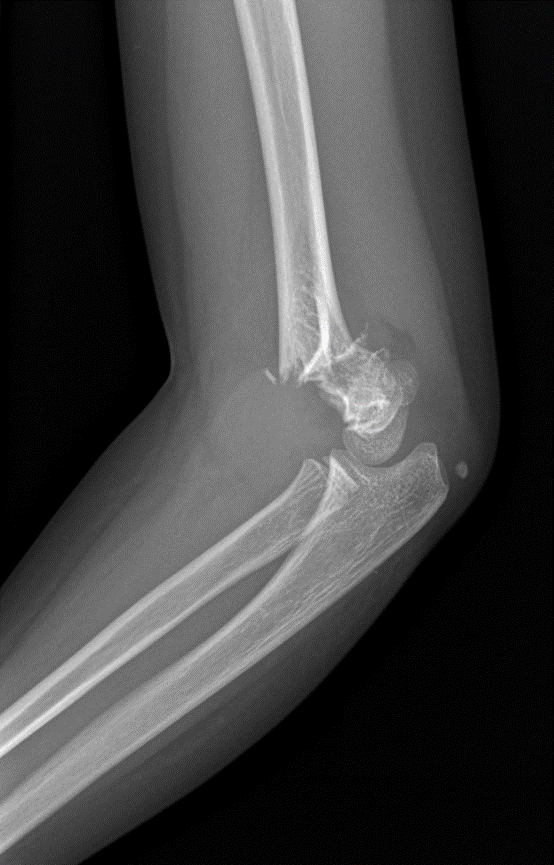

Fractura del olécranon

(lesión del codo posterior)

Las fracturas del olécranon son bastante frecuentes. Aunque generalmente ocurren por sí solos, sin otras lesiones, también pueden ser parte de una lesión más compleja del codo. En una fractura de olécranon, el hueso puede romperse ligeramente o romperse en muchos pedazos. Los pedazos de hueso rotos pueden quedar alineados o muy fuera de lugar (fractura desplazada).